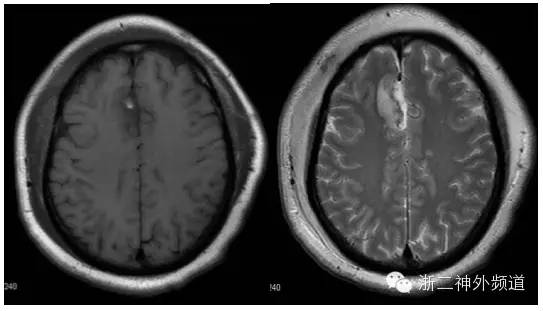

患者于3年前无明显诱因下出现头痛,以前额、双颞部为主,休息后能缓解,反复发作,但程度不重。无肢体抽搐、及发热等,未予重视。1年半前至我院查头颅MR提示“右侧额叶近中线处出血考虑,继发于血管畸形较肿瘤可能性大”(图1),CT未查,由于患者担心手术风险,予定期随访。

图1:T1像显示右侧纵裂高、等混杂信号的病灶,T2像显示高低混杂信号,无明显强化。